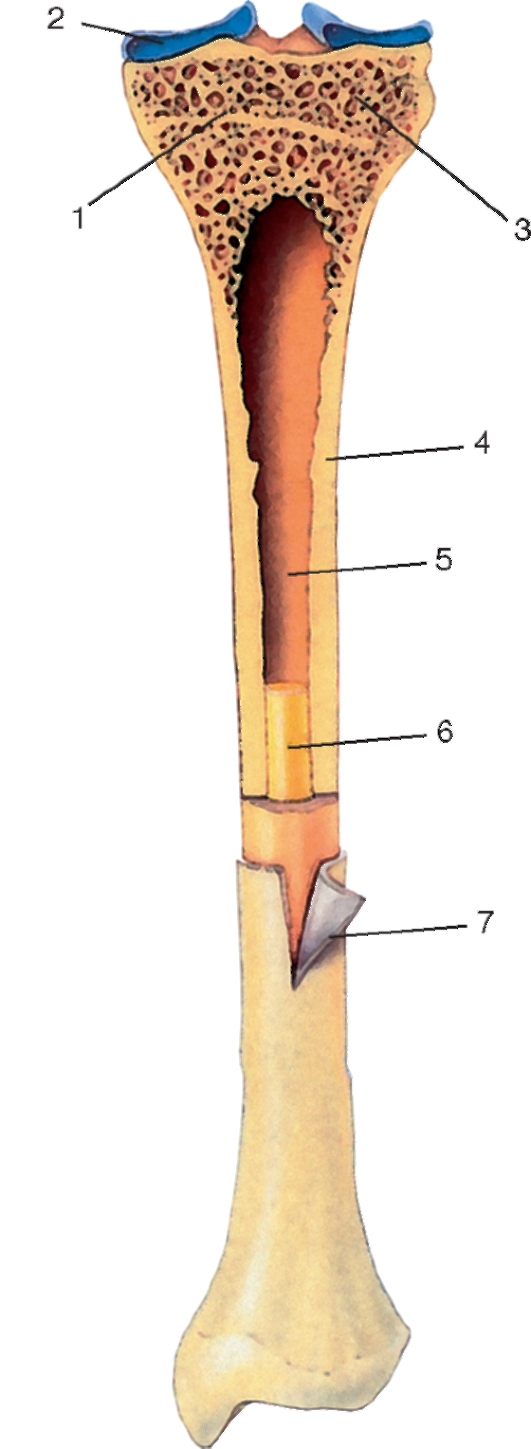

Изучение костного мозга: анатомия и функции